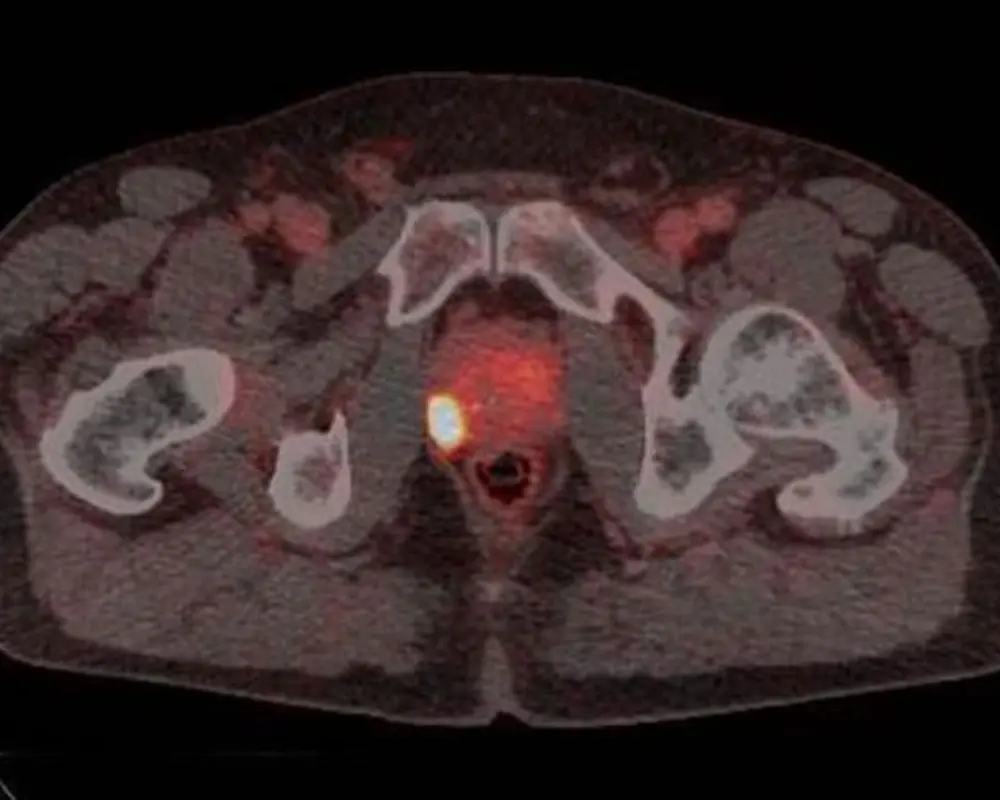

Each prostate MRI scan is performed using advanced imaging techniques designed to capture clear detail in a small and sensitive area of the body. In some cases, your provider may request an MRI of Prostate in Houston TX with contrast to highlight specific areas more clearly. This imaging is commonly used to guide biopsy decisions, assess known findings, or monitor changes over time. Whether you are visiting from Houston or nearby areas including Richmond, the goal is to provide clear results that support confident and timely care decisions.

Prostate MRI helps identify areas linked to prostate cancer. It shows suspicious regions and supports early detection when further testing is needed.

Prostate MRI helps assess if cancer has spread beyond the prostate. It gives important detail that helps guide treatment planning and next steps.